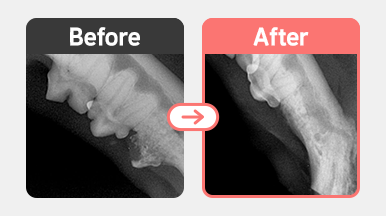

치과용 X-ray 검사 결과 PD4 M0 치주염과 함께 치아흡수성병변(FORL)이 확인되었습니다.

이 중 일부는 치근이 이미 흡수된 Type 2 양상으로 Crown Amputation(치관 절제술)이 적합한 병변이었고,

나머지 병변은 치근 손상과 치조골 변화가 진행되어 외과적 발치가 필요했습니다.